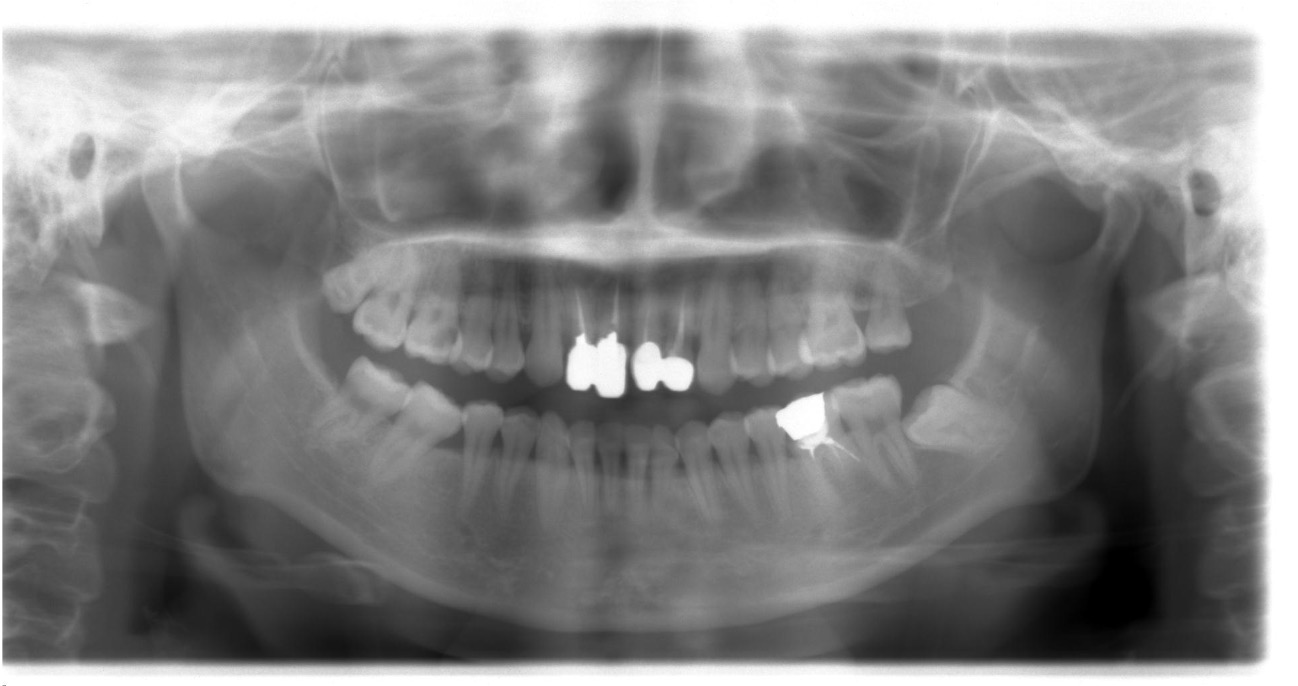

インプラント・

メタルボンドの症例

| 年齢・性別 | 54歳・男性 |

|---|---|

| 治療期間 | 6ヶ月 |

| 治療内容 | インプラント・メタルボンド・保険 |

| 治療本数 | 20本 |

| 治療費用 | インプラント(330,000円(税込)×4本) +メタルボンド(132,000円(税込)×6本) +保険治療 |

| 副作用等 | 外科手術により腫れが生じることがあります。 手術範囲や方法により異なりますが、 次第に腫れが引いてくることがほとんどです。 |